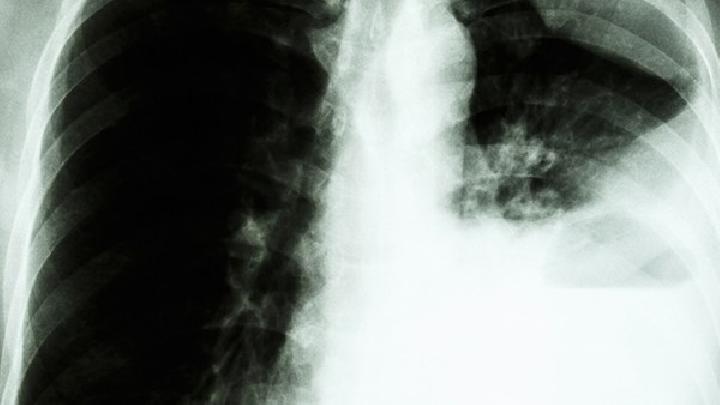

為什么肺癌不傳染?

首先,我們應該知道肺癌是一種癌癥,它是否是一種傳染病,它是否會被感染,然后我們應該找出癌癥是否會被感染。這個問題早就被提出了,并進行了大量的觀察和研究。

通過相當長時間的觀察,人們做過將癌癥動物和健康動物放在一起的實驗。

不同類型的癌癥患者在醫院長期住在病房;癌癥患者和非癌癥患者長期住在同一病房,沒有直接感染。醫務人員長期接觸癌癥患者,癌癥發病率沒有上升。

癌癥患者長期與家庭生活在一起,沒有感染。因此,可以認為癌癥通常是無傳染性的。

癌細胞與他人皮膚和消化道接觸是否會種植和存活尚未得到證實。即使將一種動物的癌細胞埋在另一種動物的組織中,其他動物也很難患癌癥。由于動物,特別是人類自身,有強烈的排他反應,人體很難接受外部事物,這也是當今器官移植難以成功的問題之一。